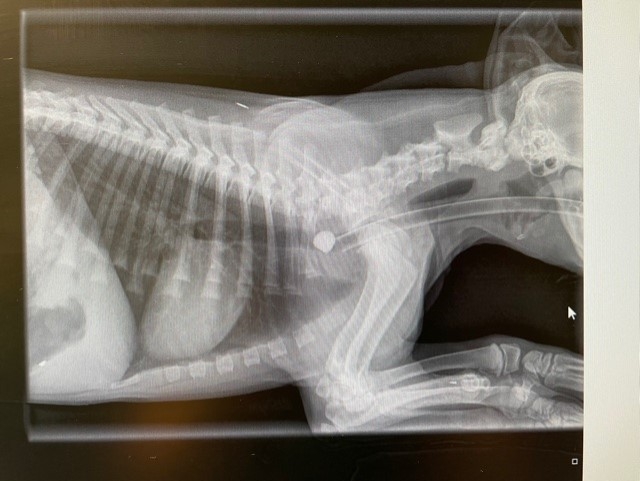

Sadly, there’s nothing new about a dog being injured by a stick. However, a mischievous spaniel puppy has given an old story a 21st Century twist when he required specialist vet treatment after swallowing a USB stick!